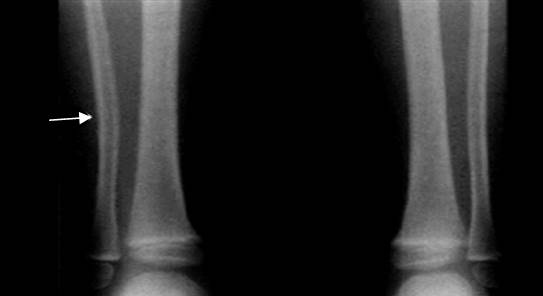

Fig 67. Deformidad plástica.

Rx AP comparativa. Sutil desviación medial en la diáfisis del peroné, por deformidad plástica.